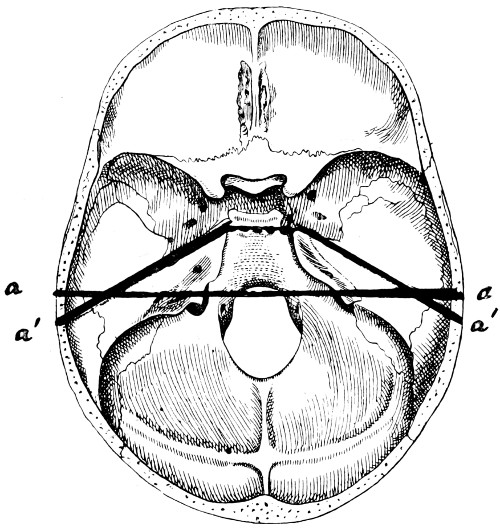

| 28. Illustrating the lines along which forces received on the vault are transmitted to the base | 69 |

| 29 A and B. The base of the skull and the base as seen on transillumination | 70, 71 |

| 30. Plan of the base of the skull | 77 |